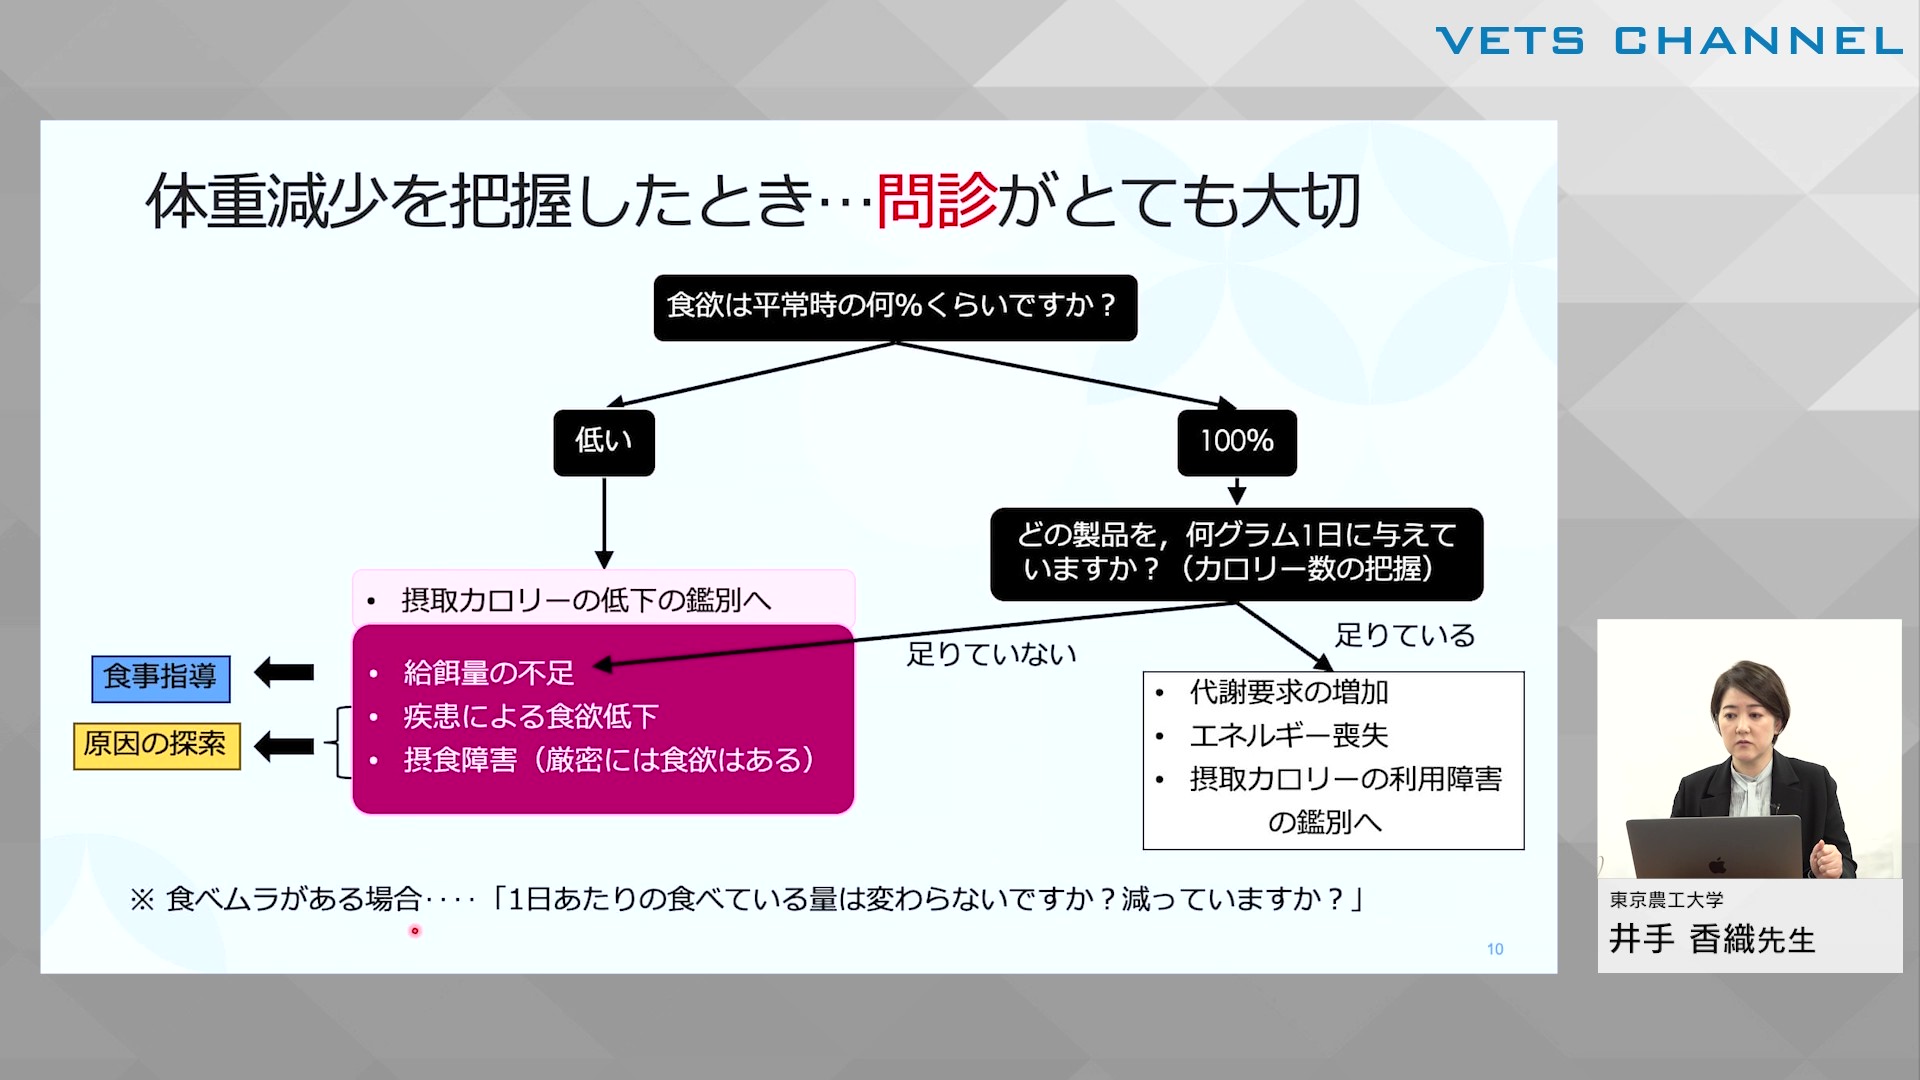

細かな変化を見落とさない!体重減少から疑う疾患アプローチ「摂取量減少」

- セミナー

- 内科全般

- 犬

- 猫

井手 香織先生 (東京農工大学 獣医内科学研究室)

52分

2025/07/25